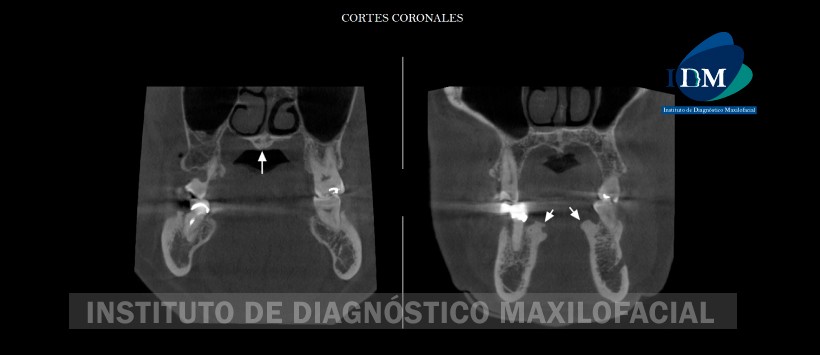

A la evaluación de la tomografía volumétrica (CBCT) en cortes coronales (Figura 2), sagitales (Figura 3), axiales (Figura 4) y transaxiales (Figura 5, 6 y 7) se evidencia presencia de múltiples excrecencias óseas de forma lobulares localizados en reborde alveolar de tabla ósea lingual en zonas de piezas 35, 34, 33, 32, 43, 44 y 45; compuesto por presencia de hueso compacto. Por otro lado, se visualiza una excrecencia ósea de hueso compacto de una amplia base localizada en rafe medio del paladar. Así mismo, se aprecia la presencia de excrecencias en el extranjero al nivel de la tabla ósea vestibular en zonas de piezas 17, 13, 23 y 26.